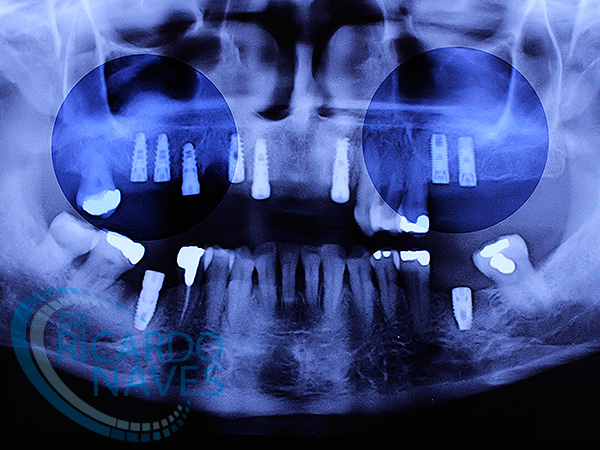

Recambio oportuno de la dentición con elevación de seno bilateral por periodontitis crónica avanzada generalizada.

Tomografía post exodoncias con marcadores radio opacos en prótesis de trabajo.